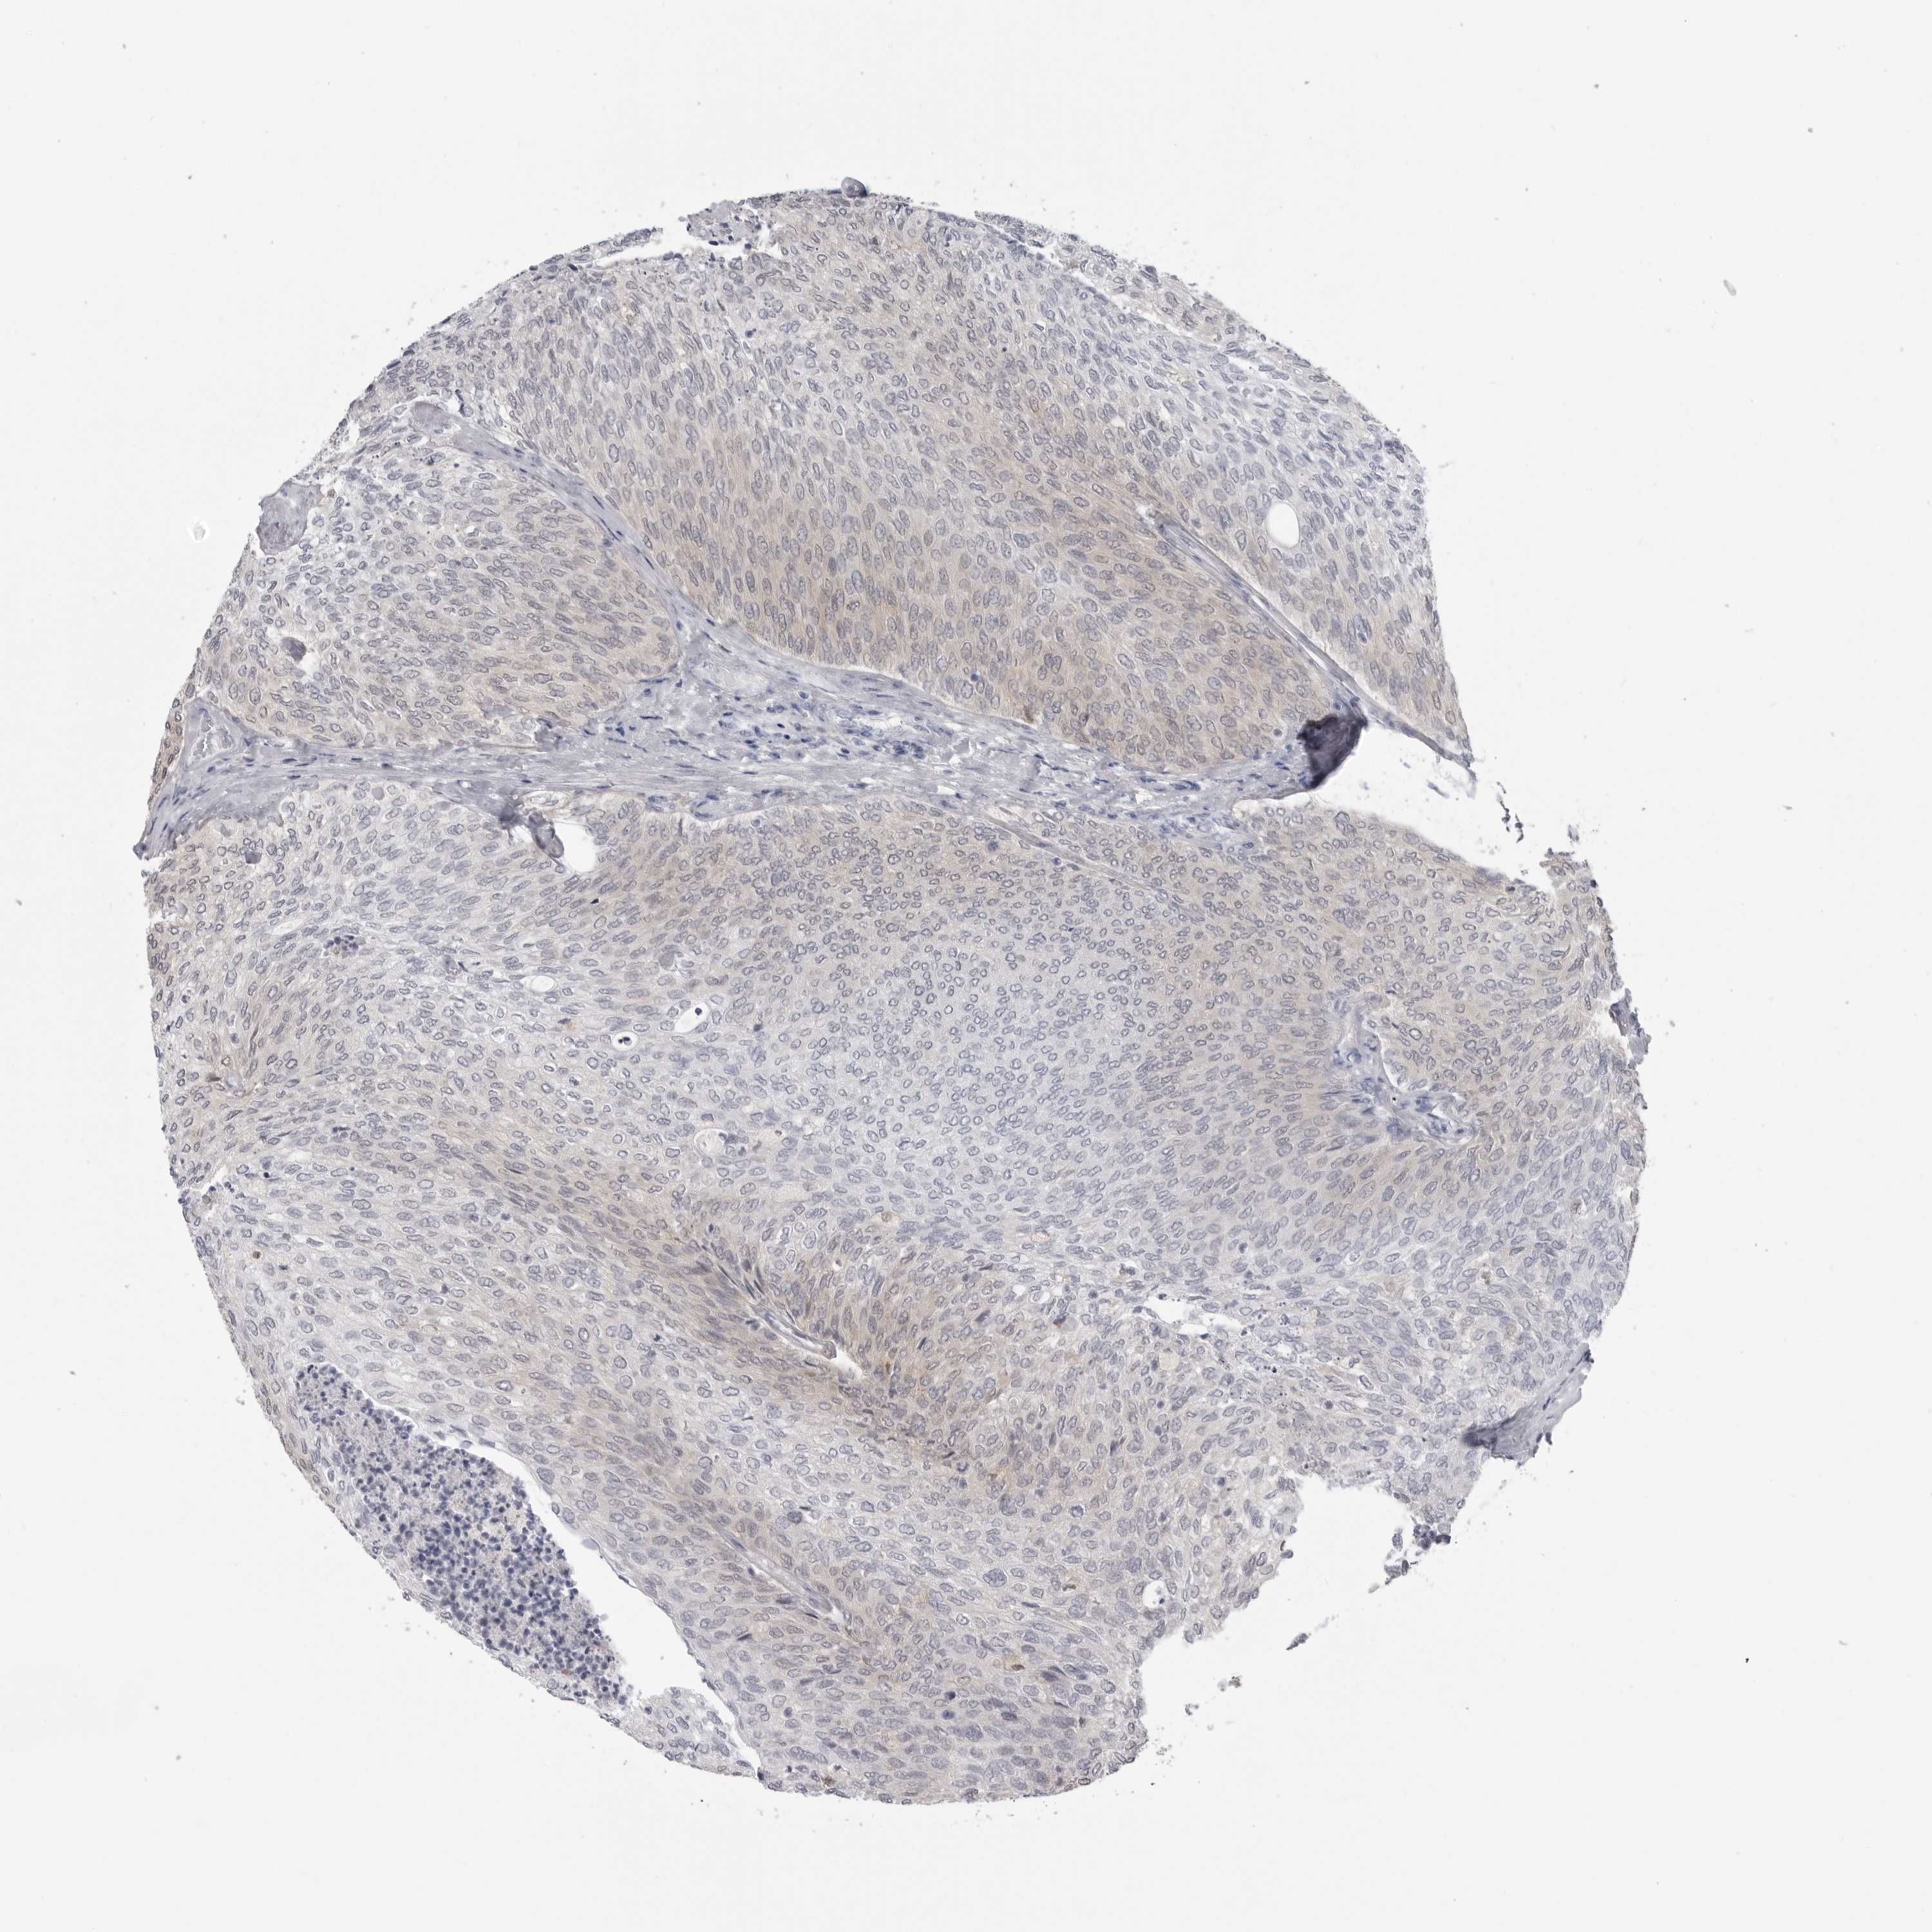

UROTHELIAL CANCER - Protein expressioni

A mouse-over function shows sample information and annotation data. Click on an image to view it in a full screen mode. Samples can be filtered based on level of antibody staining by selecting one or several of the following categories: high, medium, low and not detected. The assay and annotation is described here.

Note that samples used for immunohistochemistry by the Human Protein Atlas do not correspond to samples in the TCGA dataset.

Antibody stainingi

Antibody staining in the annotated cell types in the current human tissue is reported as not detected, low, medium, or high, based on conventional immunohistochemistry profiling in selected tissues. This score is based on the combination of the staining intensity and fraction of stained cells.

Each image is clickable and will lead to virtual microscopy that enables deeper exploration of all samples and also displays staining intensity scores, fraction scores and subcellular localization as well as patient and tissue information for each sample.

Antibody HPA023204

Antibody HPA027776

Urothelial carcinoma, Low grade

Urothelial carcinoma, High grade